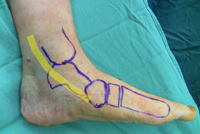

El lugar más común del dolor es alrededor del tendón tibial posterior (línea amarilla), que se extiende a lo largo de la parte trasera e interna del pie y el tobillo.